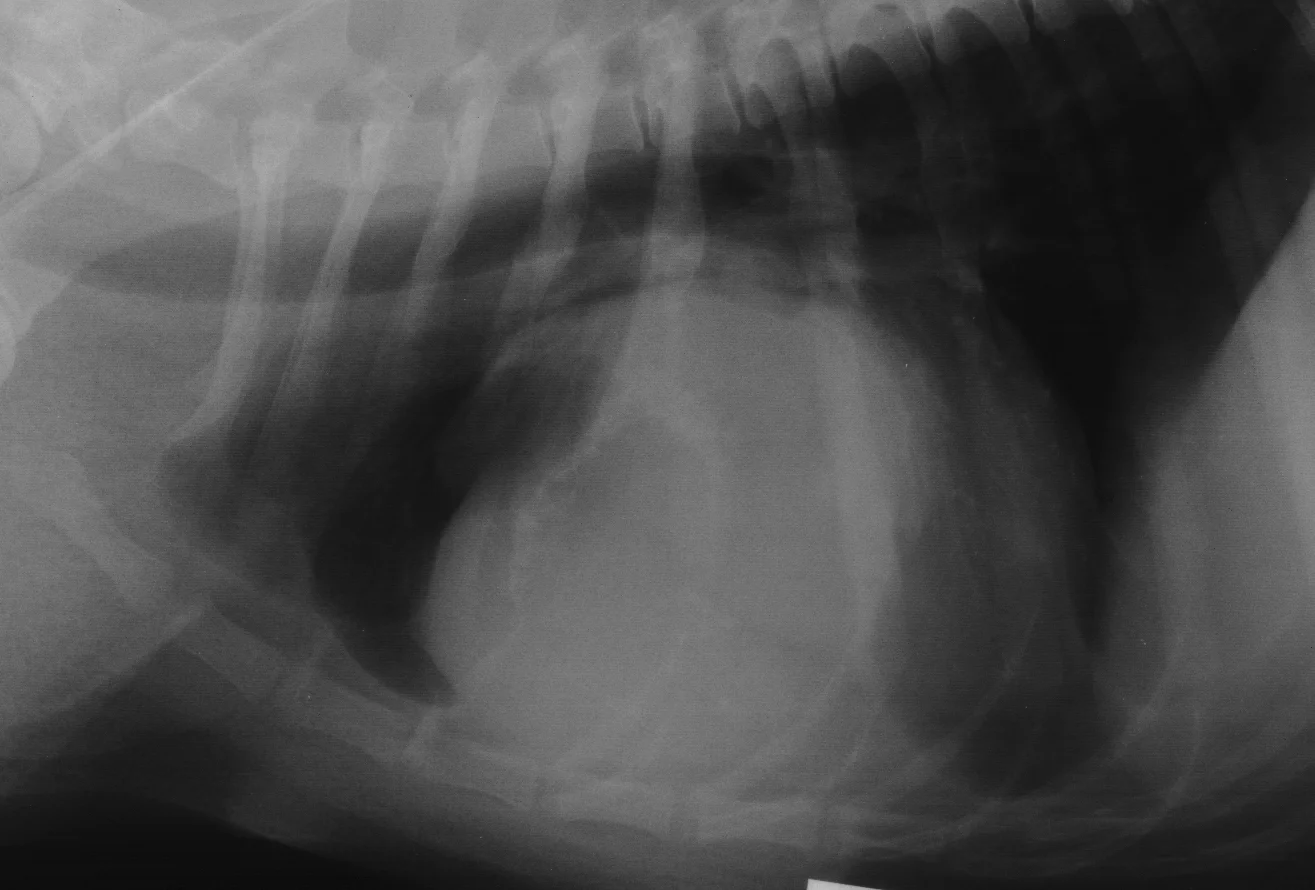

Figure 1 from Osteochondroma of the Rib a rare radiological apeareance

Figure 1 from Osteochondroma of the Rib a rare radiological apeareance Rib Bone Tumor Types of primary cancerous chest wall tumors include: Forms in cartilage and can spread to bones, usually your. Rib neoplasms are a diverse group of benign and malignant entities, which often makes determining an accurate diagnosis. These tumors may cause pain that gets worse and not better. Benign bone tumors are bone tumors that are not cancerous. Other types happen. Rib Bone Tumor.

(A) A plain radiograph showing the bone tumor with ballooning on the Rib Bone Tumor These tumors may cause pain that gets worse and not better. Types of primary cancerous chest wall tumors include: Forms in cartilage and can spread to bones, usually your. Chest wall cancer is cancer of the bone, cartilage, or soft tissue that protects and supports the organs in the chest cavity. The spectrum of rib lesions ranges from benign entities. Rib Bone Tumor.